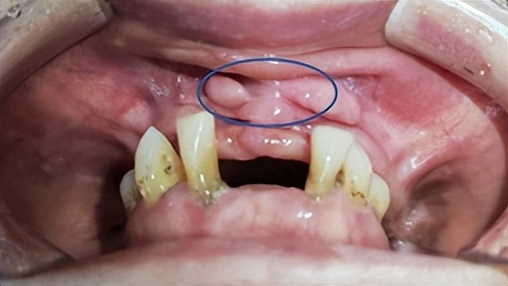

不久前,六十七岁的陈大妈因戴上颌活动假牙吃东西疼、假牙在口腔里戴不牢,在女儿的陪同下来到浙二医院口腔修复科,找到董研主任诊疗。

陈大妈口内上颌可摘义齿已经佩戴了十余年,虽然多颗人工牙脱落但咀嚼时没有不舒服,所以很多年没去看医生复诊。最近一年多,她发现自己的上牙床长出了很多“肉赘”。开始时不疼就没在意,而最近一段时间假牙就根本不能用了。戴着义齿吃东西牙床就痛,而且义齿也戴不牢,吃东西会脱落,已经影响到大妈的饮食和身体健康。

经董研主任医师的仔细问诊和口腔检查,发现陈大妈口腔里那些“肉赘”是不良增生物,需要马上切除再考虑重新制作义齿。后经病理检查证实确是良性肿物。

陈大妈这个病例告诉大家:由于牙齿缺失后牙槽骨终生不断的吸收,可造成可摘义齿的基托边缘变长从而压迫周围软组织,导致牙槽黏膜的增生有时甚至恶变。因此, 戴义齿应遵医嘱定期复查。